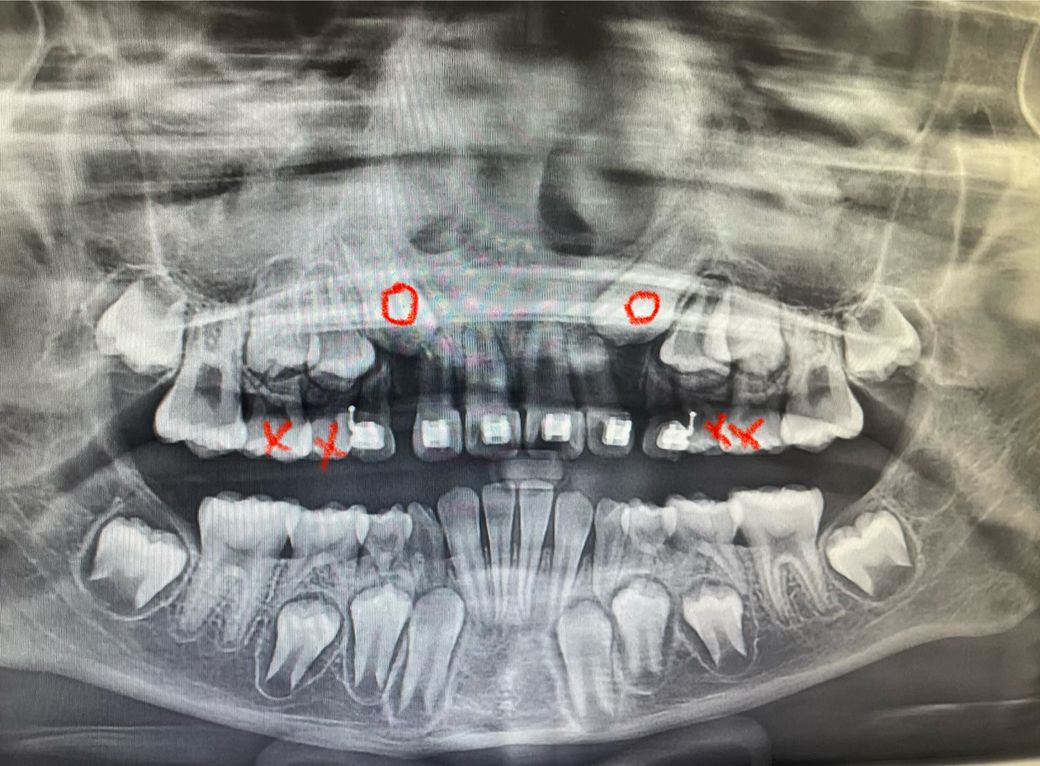

만10세 여자아이 치아 엑스레이 입니다. 교정선생님께서 송곳니 방향이 앞니로 향해있는게 좋지 않아 x표한 유치두개씩 뽑아서 동그라미표 되어있는 송곳니 방향을 틀어보자고 하셨는데 그렇게 하는것이 좋을까요? 선생님께서는 적극적이지는 않으시고 그렇게 하는것은 옵션이라고 하셨습니다.

상악 견치 맹출 방향 좋지 못해 교정적으로 견인 가능성 있어보입니다. 경과관찰 진행해볼수도 있으나 매복될 시 인접치의 치근 흡수 등의 가능성 있으므로 견인하여 재위치로 교정하시는 것이 나으리라 사료됩니다. 자세한 치료 계획은 꼭 담당 교정 선생님과 상의하시기를 바랍니다.

맹출유도를 위해 의도적으로 유치를 미리 빼주는 겁니다 적극적으로 개입하지 않고 지금 상태 그대로 두었을때 나중에 송곳니가 뻐드러져 나온다면 그때가서 그 부분 추가적으로 교정해줄 수 있는 방법은 있습니다